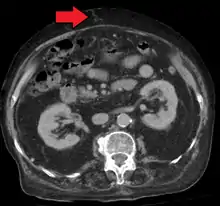

Portal hypertension due to cirrhosis resulting in revascularization of the umbilical vein

A dilated portal vein (diameter of greater than 13 or 15 mm) is a sign of portal hypertension, with a sensitivity estimated at 12.5% or 40%.[18] On Doppler ultrasonography, a slow velocity of <16 cm/s in addition to dilatation in the main portal vein are diagnostic of portal hypertension.[19] Other signs of portal hypertension on ultrasound include a portal flow mean velocity of less than 12 cm/s, porto–systemic collateral veins (patent paraumbilical vein, spleno–renal collaterals and dilated left and short gastric veins), splenomegaly and signs of cirrhosis (including nodularity of the liver surface).[17]

In addition, a widened (dilated) portal vein as seen on a CT scan or MRI may raise the suspicion about portal hypertension. A cutoff value of 13 mm is widely used in this regard, but the diameter is often larger than this is in normal individuals as well.[9]